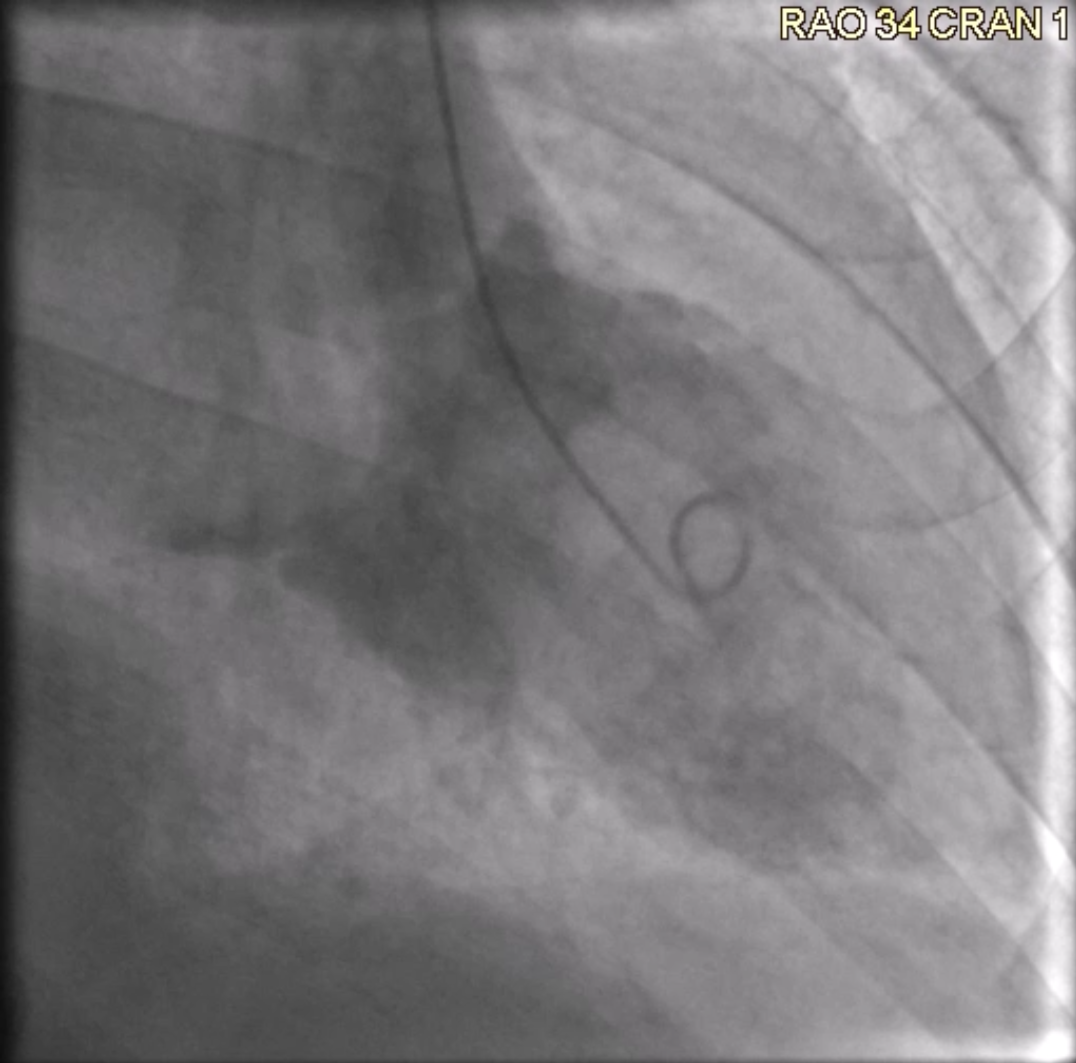

Cardiac Catheterization. Angiography was requested as a pre-procedural workup, which showed normal coronary arteries and branches supplying the left atrial mass. A small LV gram (Figure 1, Video 1) showed global cardiomyopathy with moderately reduced LV ejection fraction and a globular structure prolapsing into the LV during diastole and retracting during systole.

Video 1. Left ventriculogram with mxyoma.

The principal method for myxoma diagnosis is echocardiography. Echo provides an excellent evaluation of morphology, size, pedunculation origin, involvement of mitral valve leaflets, and obstruction of the LV outflow tract. LV angiography may add little clinical benefit for diagnosing myxoma; however, on initial catheter insertion into the LV for end diastolic pressures, our catheter was vertical in fashion, and seemingly caught behind the papillary muscle. At this point we shot a 10 cc ventriculogram to ensure the shaft of our pigtail was not in contact with the myxoma before pulling back the catheter into the aorta. The LV gram clearly demonstrated a large globular structure protruding into the ventricle during diastole. After, we inserted an .035-inch regular J-wire through the pigtail and slowly retracted the catheter back into the aorta, monitoring it with the goal of not interrupting left atrial outflow and disturbing the myxoma.

In contemporary cardiac catheterization, left ventriculography may provide little benefit in diagnosing ejection fraction and mitral valve insufficiency. Modern echocardiography has become the gold standard in identifying structural disease and heart function. However, in our case, the use of left ventriculography helped to identify the catheter position in relation to the myxoma and provided a layout on where we wanted our catheter to be on pullback.

An LV gram can provide some utility in patients with myxoma in determining catheter position to ensure no disruption occurs between the catheter and tumor.